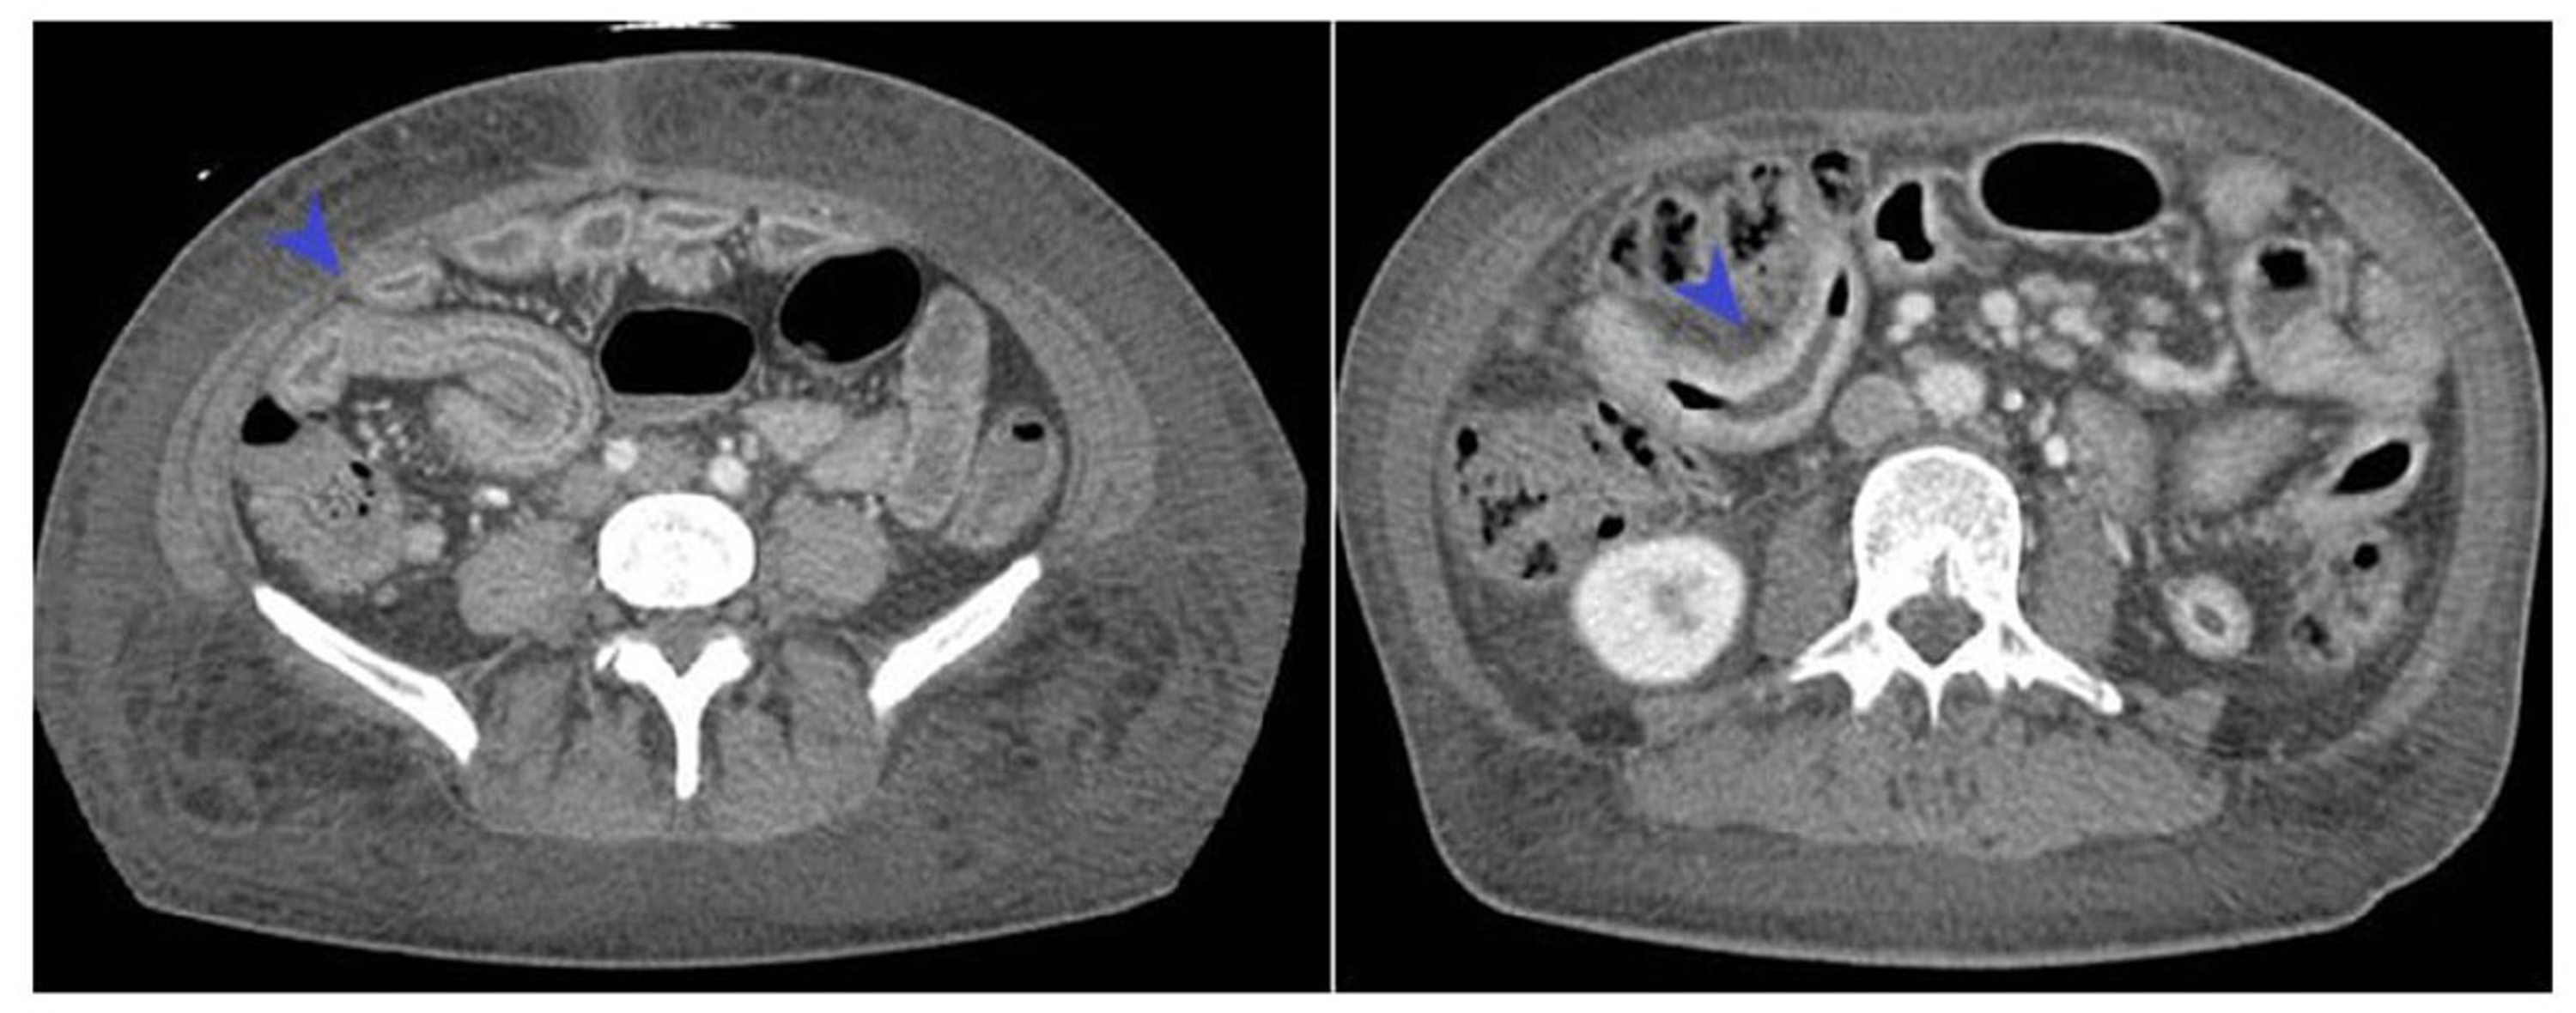

Crohn's disease. Contrastenhanced CT scan shows distal ileal loops Crohn's Disease Jejunum Crohn’s disease (cd) is a chronic inflammatory gastrointestinal (gi) disorder with variable presentations. Jejunoileitis is a form of crohn’s disease which causes inflammation in the jejunum (the upper half of the small intestine). Inflames the middle part of the small intestine (jejunum) crohn's (granulomatous) colitis: Isolated jejunal crohn’s disease (ijcd) is a rare manifestation of small bowel inflammatory disease described. Crohn's Disease Jejunum.

(A) Computed tomography enterography (CTE) in a patient with Crohn's Crohn's Disease Jejunum Isolated jejunal crohn’s disease (ijcd) is a rare manifestation of small bowel inflammatory disease described in a few case. Jejunoileitis is a rare type of crohn’s disease in the small intestine of the gastrointestinal tract. Inflames the middle part of the small intestine (jejunum) crohn's (granulomatous) colitis: Crohn disease is a form of inflammatory bowel disease (ibd) like ulcerative colitis,. Crohn's Disease Jejunum.

Comb sign and target sign Crohn disease Radiology at St. Vincent's Crohn's Disease Jejunum The added value of diffusion weighted imaging for. Isolated jejunal crohn’s disease (ijcd) is a rare manifestation that may. Crohn disease is an immunologically. Jejunoileitis is a form of crohn’s disease which causes inflammation in the jejunum (the upper half of the small intestine). Inflames the middle part of the small intestine (jejunum) crohn's (granulomatous) colitis: Crohn’s disease (cd) is. Crohn's Disease Jejunum.